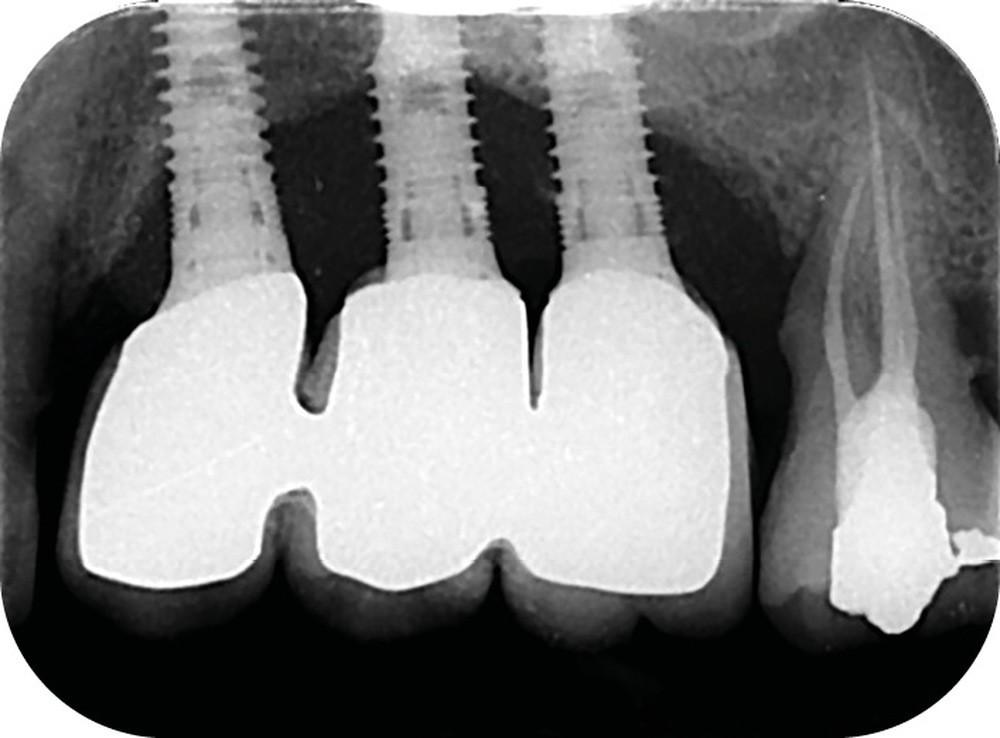

Le nombre d’implants influe aussi sur la survenue de péri-implantite. Dans les reconstructions plurales, l’implant médian est plus à risque de perte osseuse marginale et de péri-implantite [17] (fig. 6 et 7).

Enfin, la conception prothétique elle-même est à réfléchir, que ce soit en termes de profil d’émergence [18, 19] (pas de surcontour par exemple) (fig. 8) que d’accès à l’hygiène [20, 21] (fig. 9).